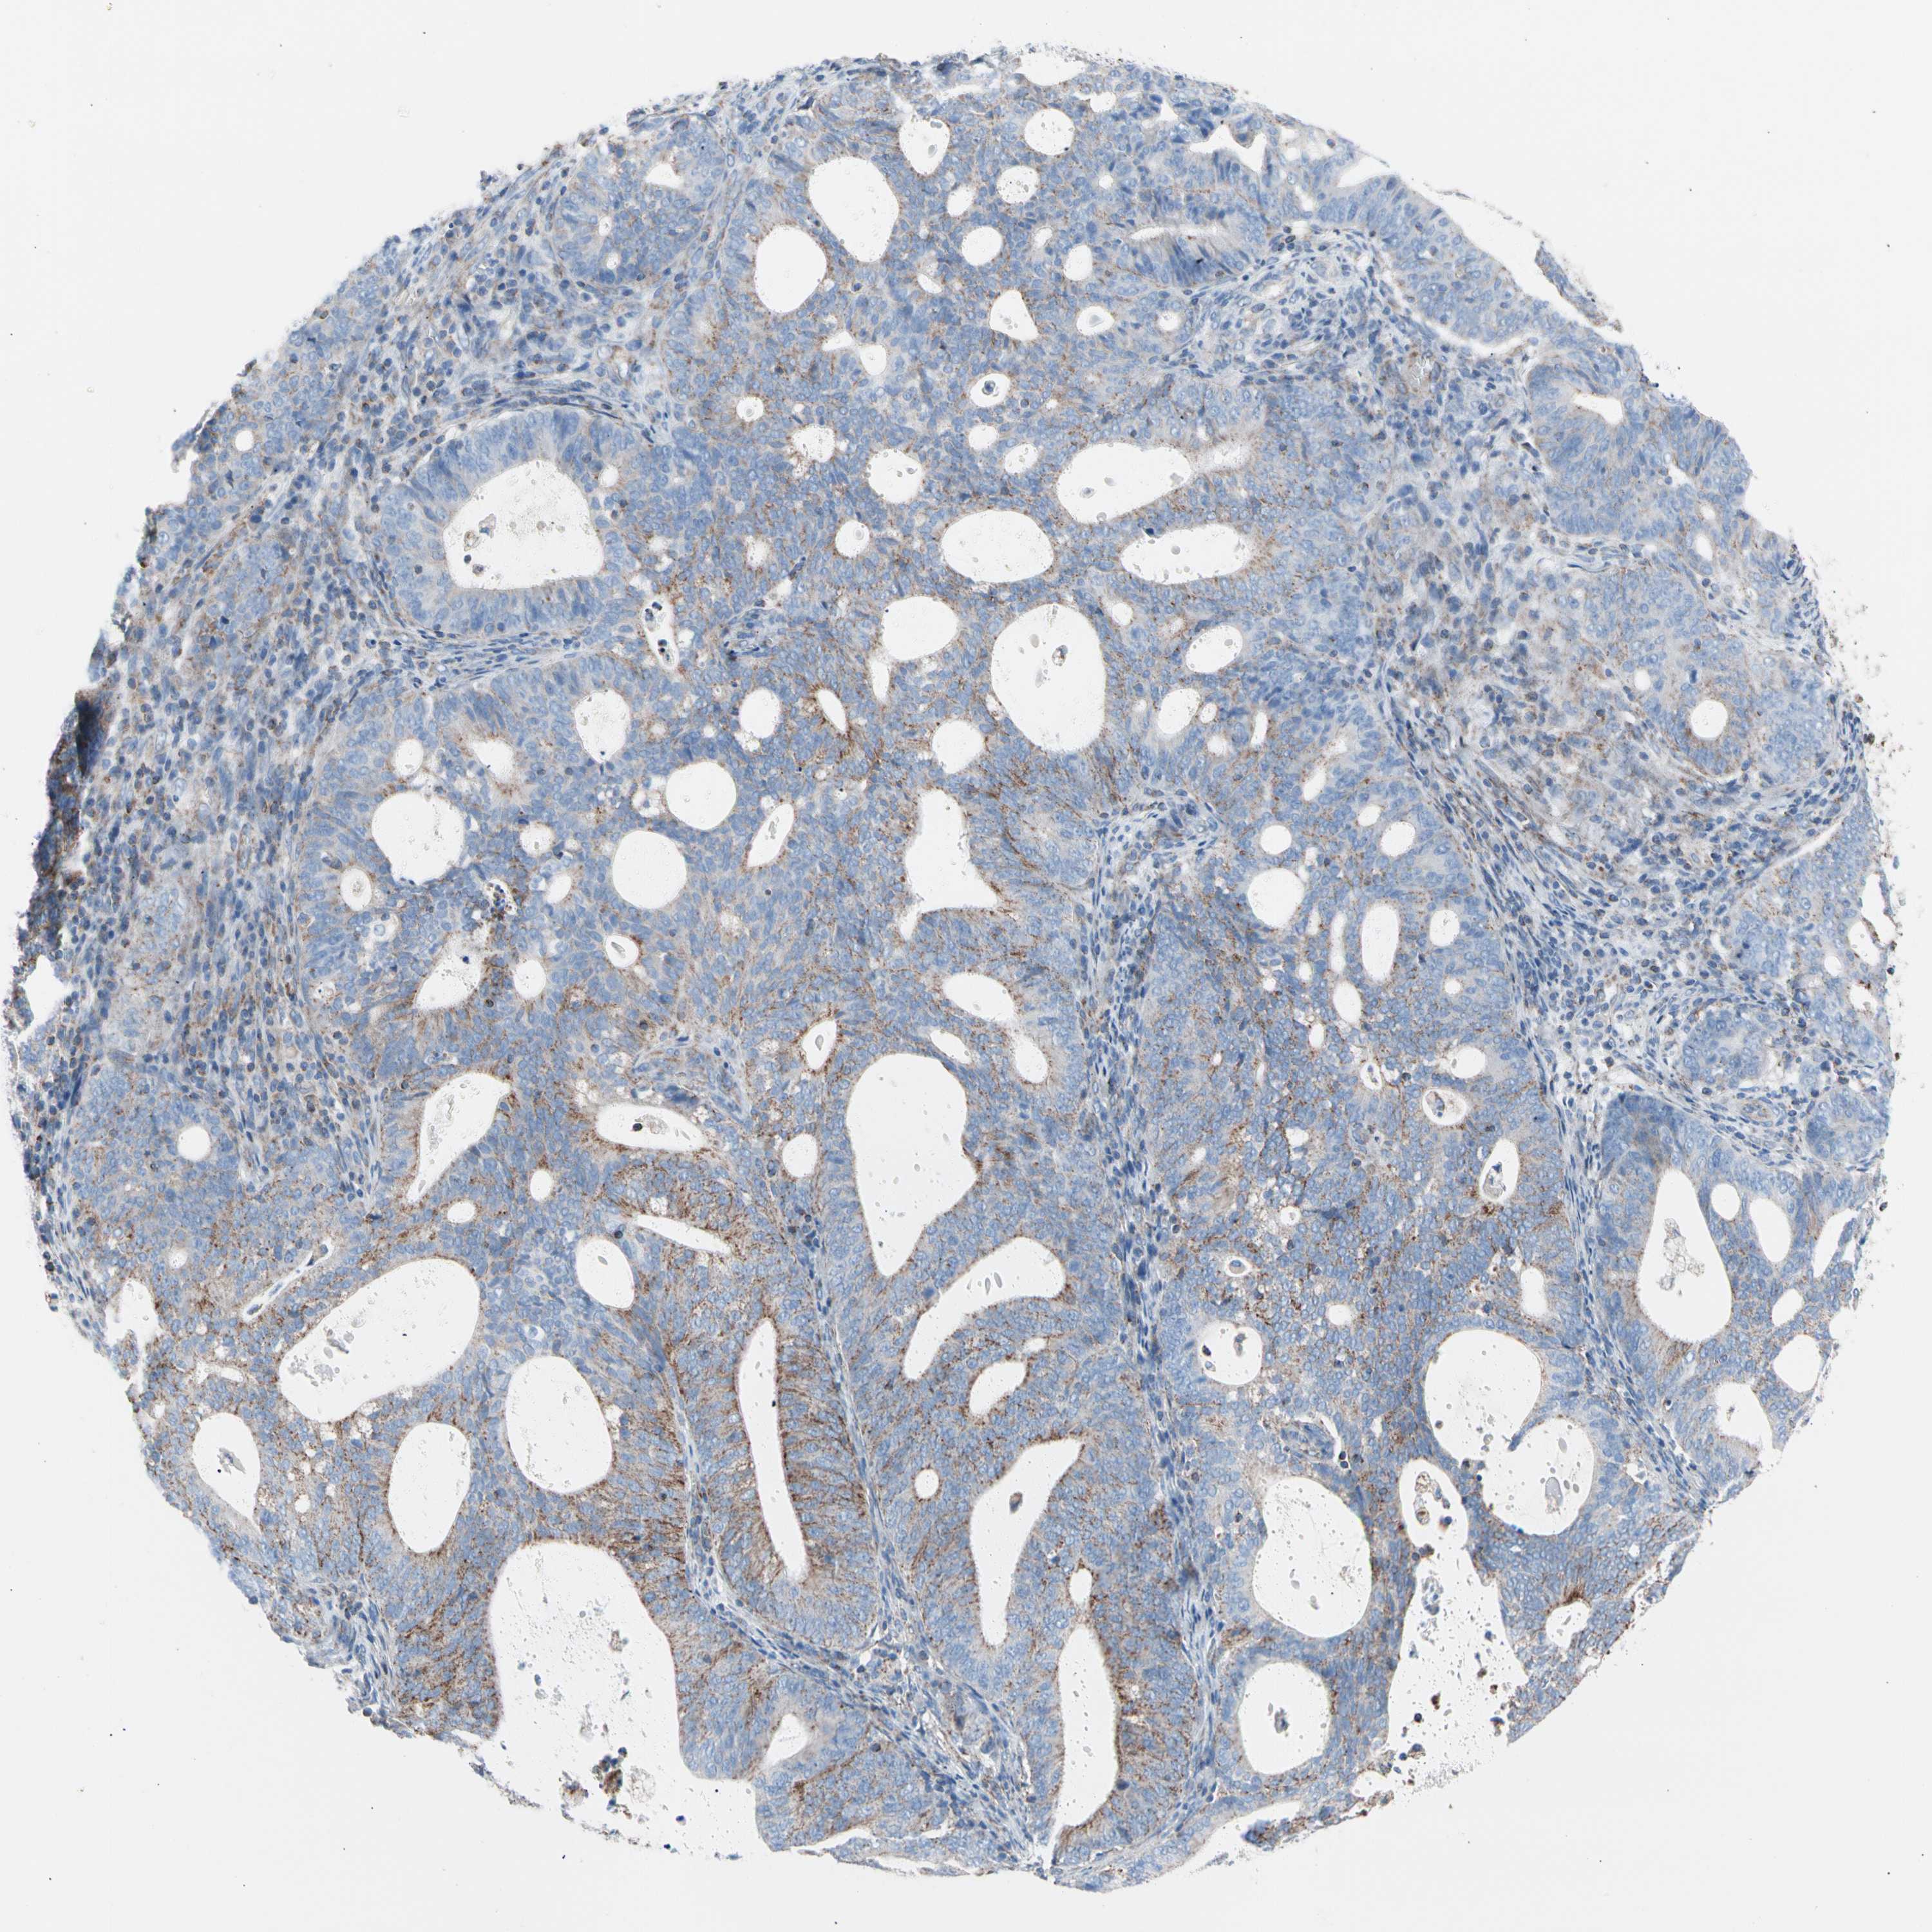

ENDOMETRIAL CANCER - Protein expressioni

A mouse-over function shows sample information and annotation data. Click on an image to view it in a full screen mode. Samples can be filtered based on level of antibody staining by selecting one or several of the following categories: high, medium, low and not detected. The assay and annotation is described here.

Note that samples used for immunohistochemistry by the Human Protein Atlas do not correspond to samples in the TCGA dataset.

Antibody stainingi

Antibody staining in the annotated cell types in the current human tissue is reported as not detected, low, medium, or high, based on conventional immunohistochemistry profiling in selected tissues. This score is based on the combination of the staining intensity and fraction of stained cells.

Each image is clickable and will lead to virtual microscopy that enables deeper exploration of all samples and also displays staining intensity scores, fraction scores and subcellular localization as well as patient and tissue information for each sample.

Antibody HPA007043

Antibody HPA007044

Antibody CAB010052

Staining

High

Medium

Low

Not detected

Intensity

Strong

Moderate

Weak

Negative

Quantity

>75%

75%-25%

<25%

None

Location

Nuclear

Cytoplasmic/membranous

Cytoplasmic/membranous,nuclear

Adenocarcinoma, NOS